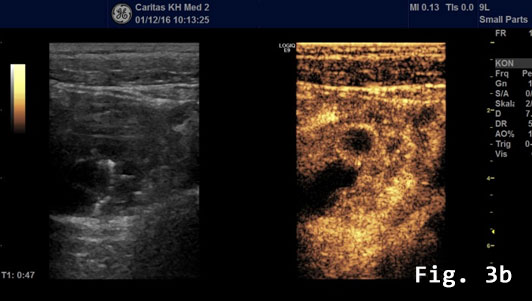

Contrast enhanced ultrasound (CEUS) showed a rapidly and heterogeneously enhancing lesion during the arterial and venous phases [Figure 3]. Contrast enhanced colour Doppler ultra-sound confirmed the finding.

![Endometriosis infiltrating the sigmoid colon</br> [May 2017]](http://s834315022.websitehome.co.uk/wp-content/uploads/2020/11/cotm_may2017_fig3b.jpg)